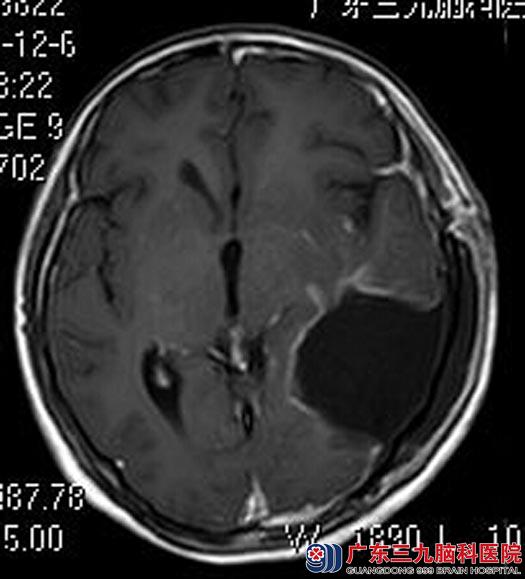

由鲁主任主刀,在唤醒麻醉、神经导航引导、电生理监测下行左侧大脑半球巨大占位性病变切除术,显微镜下见病变组织位于左侧额颞顶枕叶,呈灰褐色,质中,边界不清,血供丰富,予显微镜下超声刀分块切除,语言及肢体活动功能配合良好,功能无受损,术中快速病理结果为:高级别上皮细胞瘤,予以扩大切除肿瘤,手术顺利。术后梅梅语言及肢体功能正常。术后病理结果:节细胞胶质瘤I级。

手术后